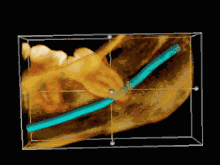

വിവേക ദന്തത്തിന്റെ സ്ഥാനം അനുസരിച്ച് കുടുങ്ങൽ അഥവാ ഇംപാക്ഷന് പലതരം ഉണ്ട്. ലംബമായതും(vertical) തിർശ്ചീനമായതും (horizontal) കോണായി (mesioangular)ചരിഞ്ഞതുമാണ് പ്രധാന തരങ്ങൾ പല ഗവേഷകരും തരം തിരിവ് നടത്തിയിട്ടുണ്ട്. പെല്ല് അൻഡ് ഗ്രിഗറി [1]എന്നിവരുടെ തരം തിരിവാണ് അതിൽ ഏറ്റവും സ്വീകാര്യമായി കരുതപ്പെടുന്നത് [2]

- സ്ഥാനം 1 - കുടുങ്ങിയ വിവേകദന്തത്തിന്റെ ഏറ്റവും മേൽ ഭാഗം ദന്തനിരയുടെ നിരപ്പിനേക്കാള് മേലെയോ അതിനൊപ്പമോ ആയിരിക്കുന്ന അവസ്ഥ

- സ്ഥാനം 2 - കുടുങ്ങിയ വിവേകദന്തത്തിന്റെ ഏറ്റവും മേൽ ഭാഗം ദന്തനിരയുടെ നിരപ്പിനേക്കാള് താഴെയും എന്നാൽ മോണയുടെ നിരപ്പിനേക്കാൾ മേലെയും ആയിരിക്കുന്ന അവസ്ഥ

- സ്ഥാനം 3 - കുടുങ്ങിയ വിവേകദന്തത്തിന്റെ ഏറ്റവും മേൽ ഭാഗം മോണയുടെ നിരപ്പിനേക്കാൾ താഴെയായി വരുന്ന അവസ്ഥ.

- നില 1- കുടുങ്ങിയ വിവേകദന്തത്തിന്റെ പല്ലിന്റെ ഒരു ഭാഗവും (ക്രൗൺ) താടിയെല്ലിന്റെ പിൻഭാഗത്തായി (റാമസ്) വന്നിട്ടില്ലാത്ത അവസ്ഥ.

- നില 2 കുടുങ്ങിയ വിവേകദന്തത്തിന്റെ പല്ലിന്റെ കുറച്ചു ഭാഗം (ക്രൗൺ) താടിയെല്ലിന്റെ പിൻഭാഗത്തായി (റാമസ്) വരുന്ന അവസ്ഥ.

- നില 2 കുടുങ്ങിയ വിവേകദന്തത്തിന്റെ പല്ലിന്റെ പകുതിയിലേറെ ഭാഗം (ക്രൗൺ) താടിയെല്ലിന്റെ പിൻഭാഗത്തായി (റാമസ്) വരുന്ന അവസ്ഥ.